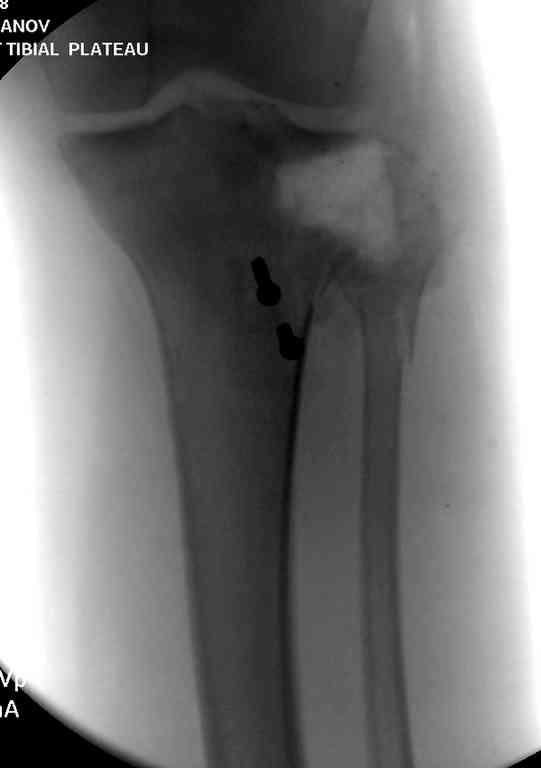

Одинокий кортикальный шуруп не удержит тибиальный бугор, сустав тибиал плато оставлен без репозиции и фиксации.

План с протезированием чересчур агрессивный, больная слишком молодая. В данный момент для удержания конструкции необходимо установить наружный фиксатор между бедром и голенью. Обработку продолжать с применением антибиотиков и вакуумирования.

Возможно, удастся сохранить из того, что осталось, или перевести больную в стационар где имееюся адекватные условия.

Здесь применение материала Plexur http://www.plexur.com для пластики при дефектах кости у больной с огнестрельной раной латерального тибиал плато с повреждением малоберцового нерва. Несмотря на интактный медиальный мышелок, для профилактики от вальгуса установлен АВФ и сделана ангиограмма.